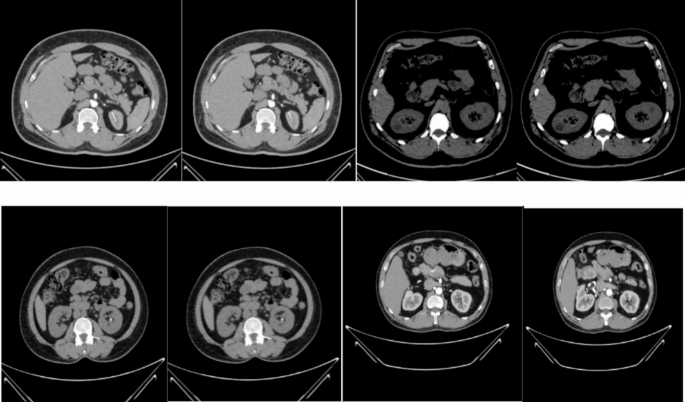

Figure 5 shows samples of the original images, and Fig. 6 illustrates samples of the enhanced images. These images clearly illustrate the improvements in image quality and details achieved by applying the MSF technique.

Samples of the original images.